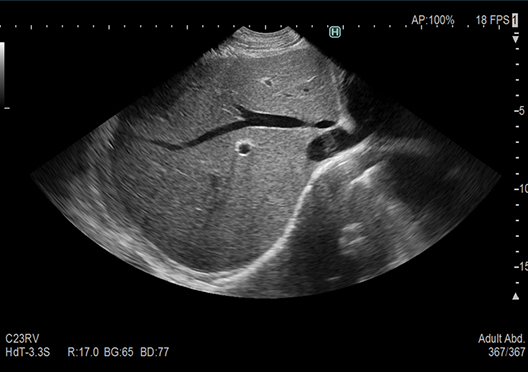

Images with "Clearer Visibility" are produced by our image processing technology that enhances tissue structure visibility. Realizes stable imaging with less patient dependency.

OFF